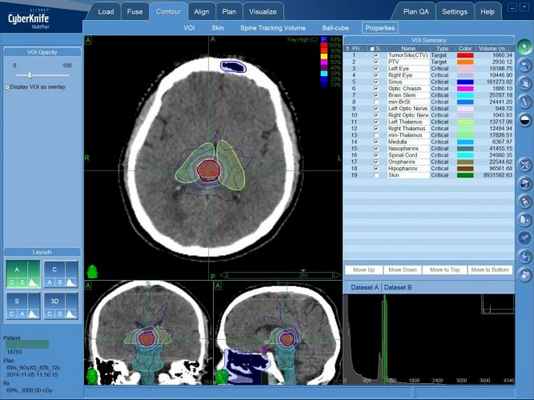

Радиохирургическая система КиберНож

При лечении большинства онкологических заболеваний головного мозга наибольшей эффективности удается достичь с применением радиохирургического метода. Радиохирургия позволяет удалить очаги новообразования в труднодоступных для хирургической операции местах. Поэтому при лечении эпендимомы головного мозга в преимущественно применяется радиохирургия на системе КиберНож.

Лечение на системе КиберНож

В случае раннего диагностирования новообразования, а также небольшого размера опухоли эпендимомы, возможно проведение дистанционного лечения — радиохирургической операции на системе КиберНож.

Для этого в процессе планирования лечения определяется требуемая форма и расположение объема, в котором будет сформирована зона равномерно высокой дозы ионизирующего облучения — она будет полностью совпадать с указанными лечащим врачом контурами опухолевого поражения. Составленная на основе данных КТ- и МРТ-исследований пространственная 3D-модель с указанием зон с минимальной и максимальной лучевой нагрузкой, передается в программный комплекс КиберНожа для расчета множества последовательно подаваемых с различных положений тонких лучей ионизирующего излучения. После этого пациент может начинать лечение эпендимомы на КиберНоже.

Лечение эпендимомы головного мозга на КиберНоже

При радиохирургии на КиберНоже не требуется специальной подготовки пациента, наркоз не проводится — пациент во время фракции (сеанса) лечения эпендимомы на КиберНоже находится в сознании. Роботизированная “рука”-манипулятор комплекса последовательно занимает указанные в плане лечения положения, в каждом из которых производится подача отдельного тонкого пучка ионизирующего излучения. После завершения фракции (15-30 минут) пациент сразу может вернуться к обычному распорядку своего дня. Количество фракций зависит от множества индивидуальных факторов.